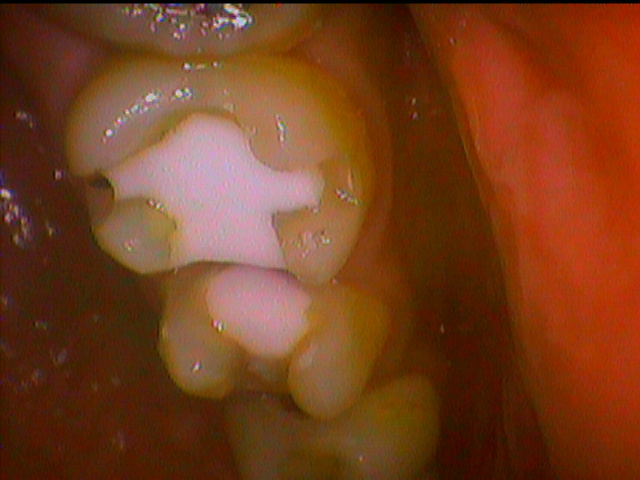

そして綺麗になった穴に強化プラスチィックにて新たに充填する処置を致しました。

研磨を綺麗に行い、ザラザラ感が解消しているかどうかも確認していただきました。特に問題がなかったので今後のメンテナンスとリスク説明を行いました。

以前に比べると外観はもちろんですがとても滑らかに綺麗な仕上がりになったと喜んでいただいてよかったです。